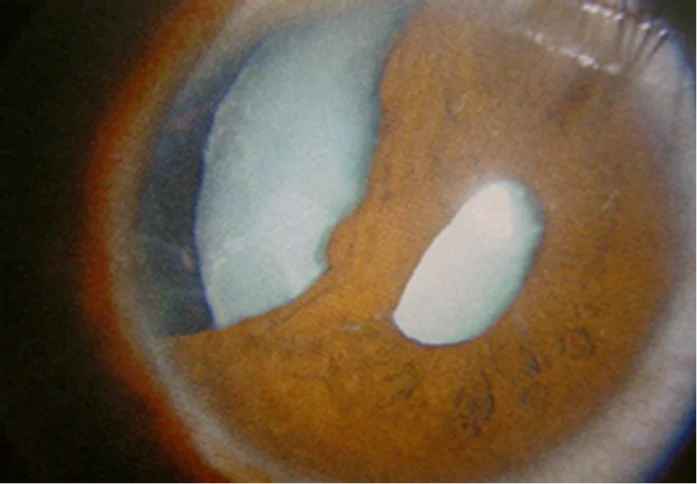

Traumatic Cataract

• Penetrating trauma